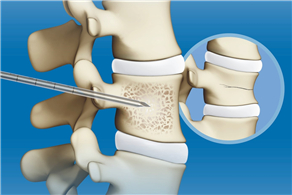

椎體成形術系統 (PKP&PVP)宣傳彩頁

發布時間:2020-08-25

椎體成形術輔助器械彩頁

發布時間:2019-11-07